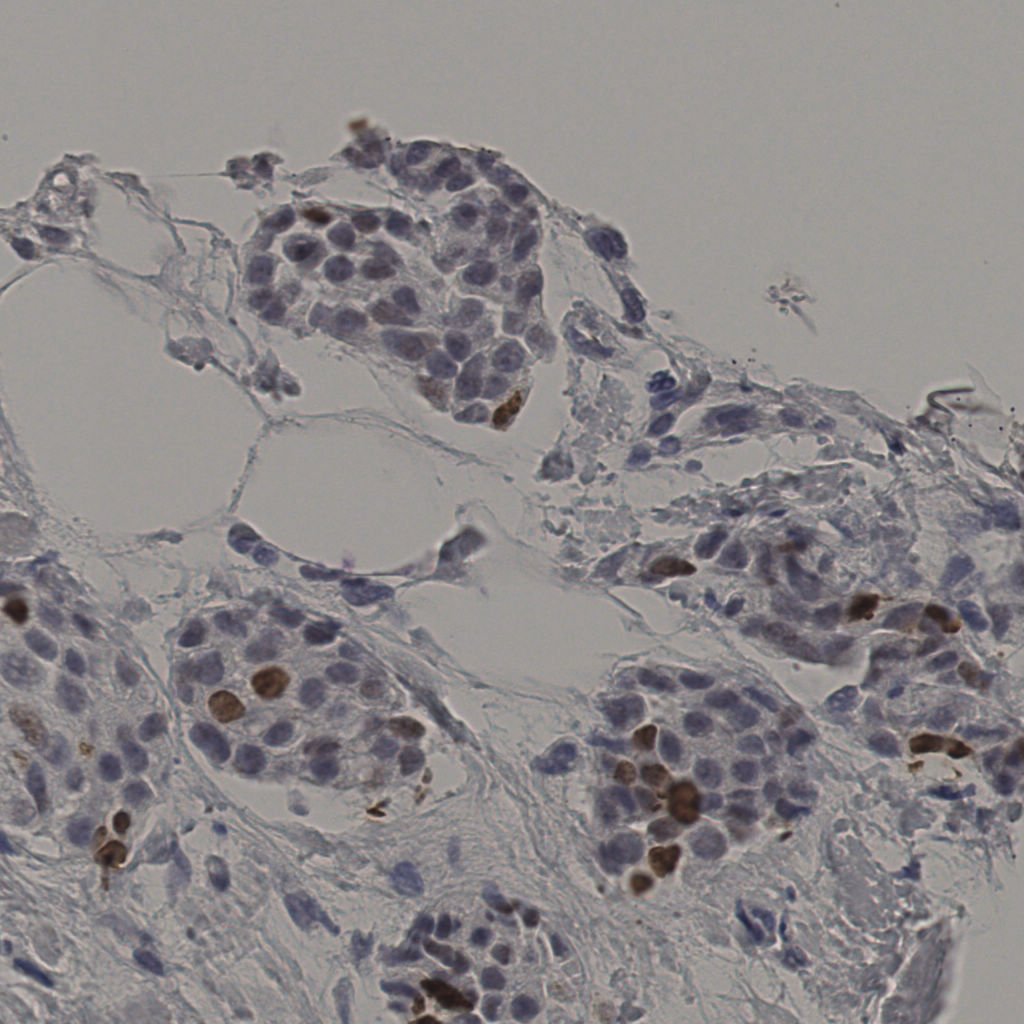

5.31%

Ki67 指数

阴 19502

阳 1093

切片统计

总切片

2970

有效

554

已标记

554

有效率

19%